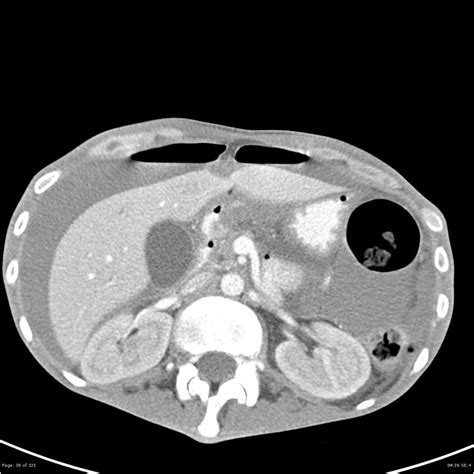

Experiencing gastrointestinal distress can be alarming, but recognizing the signs of bleeding into the stomach—medically referred to as an upper gastrointestinal (GI) bleed—is crucial for seeking timely medical intervention. This condition occurs when there is a breakdown in the protective lining of the digestive tract, leading to blood loss into the stomach or the upper part of the small intestine. Because this can range from a slow, chronic leak to a rapid, life-threatening hemorrhage, understanding the symptoms, underlying causes, and appropriate responses is vital for your health and safety.

Diagnosis and Treatment Pathways

Once a patient arrives at a medical facility, doctors act quickly to stabilize the individual, especially if blood loss has been significant. Initial steps involve assessing heart rate and blood pressure, followed by blood tests to check hemoglobin levels. If you are diagnosed with bleeding into the stomach, treatment will depend on the underlying cause.

• Endoscopic Therapy: During an endoscopy, doctors can often stop the bleeding by cauterizing the area, using clips to close a vessel, or injecting medication directly into the site.